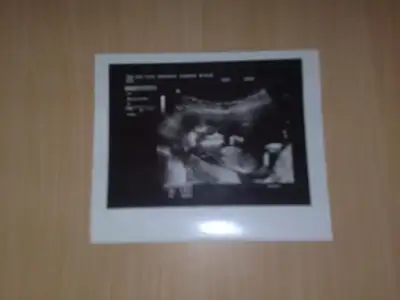

amin canımcım... ayşeee ben senin bebeğinin cinsiyeti kız diye biliyorum halbuki çooook erken bunu öğrenmek içinAllahmı söyletti neeeeeee

Daha bilniyoruz cinsiyetini hayirlisi olsun arkadasim esimin ailes kiz istiyorrr.bizimkilerde erkek istiyor ben ikisinide istiyorum